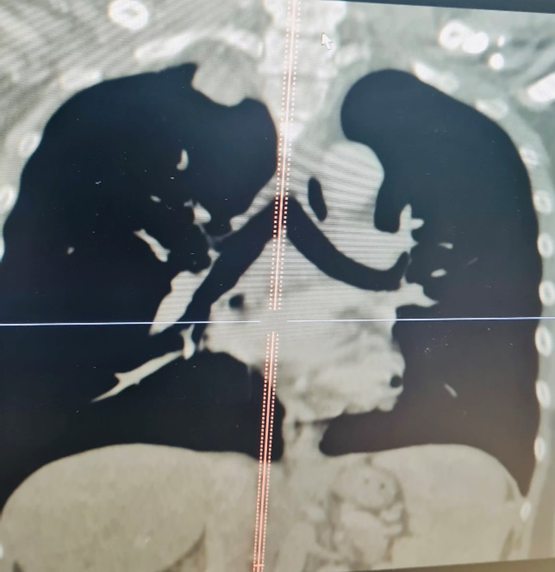

Bệnh nhân là anh Nguyễn Đức T. 40 tuổi vào viện trong tình trạng tức ngực, khó thở kéo dài, đau lưng, vai và cánh tay. Qua chụp cộng hưởng từ và cắt lớp vi tính phát hiện bệnh nhân có khối u từ trong ống sống ngực đã phát triển vào trong lồng ngực với kích thước lớn 3×4 cm. Khối u này đã phát triển vào trung thất sau ăn sát hõm đỉnh lồng ngực, đè đẩy vào bó mạch thần kinh cánh tay, đặc biệt là tĩnh mạch dưới đòn trái.

Hình ảnh khối u của bệnh nhân T. trên phim chụp cắt lớp vi tính và cộng hưởng từ